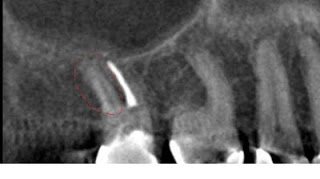

In addition to the above two radiographs, I also examined a bitewing and two traditional film radiographs which I chose not to include here. One thing that stands out is that the crown margin is placed on the buildup, not an ideal situation. You can see only two canals treated and an in tact PDL. The orifices of the canals are clearly overenlargedand the obturation does not appear to follow the root anatomy.

It appeared as if the previous operator perforated during instrumentation, not only between the mesial and distal roots, but also at the apex. In addition to these root perforations, the coronal tooth structure is clearly compromised. The patient was anxious to save the tooth since she invested in root canal treatment and a crown within the last year. I did not feel retreatment would have a good prognosis and recommended extraction. The patient was understandably reluctant about this option, and so I opted to image the tooth with CBCT for more information and better patient education.

In the below left image, I circled the missed DB canal. The below right images (one is reversed, please forgive me) display the missed DB root in the sagittal plane as well as the apical perforation and over enlargement (strip perforation) of the MB root.